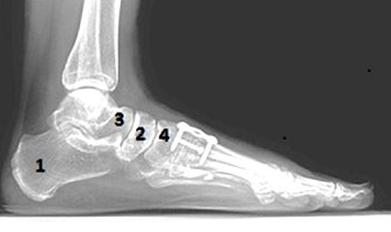

Pacjentowi, u którego dokonano amputacji stopy na poziomie stawów śródstopno-stępowych, przeprowadzono odjęcie typu